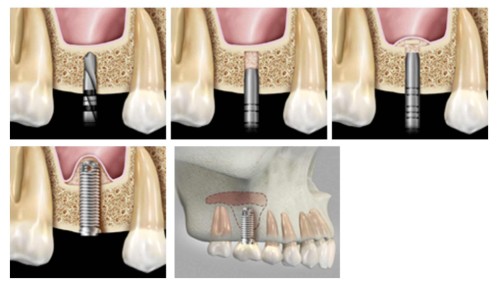

How is a sinus lift accomplished?

Most commonly, a small incision is made on the premolar or molar region to expose the jaw bone. A small opening is cut into the bone, and the membrane lining the sinus is pushed upward. The underlying space is filled with bone grafting material, either from your own body or from a other sources. Sometimes, synthetic materials that imitate bone formation are used. After the bone is implanted, the incision is sutured and the healing process begins. After several months of healing, the bone becomes part of the patient’s jaw and dental implants can be inserted and stabilized in the newly formed sinus bone.

If enough bone between the upper jaw ridge and the bottom of the sinus is available to sufficiently stabilize the implant, sinus augmentations and implant placement can sometimes be performed as a single procedure. If not enough bone is available, the sinus augmentation will have to be performed first, then the graft will have to mature for up to several months, depending upon the type of graft material used. Once the graft has matured, the implants can be placed.